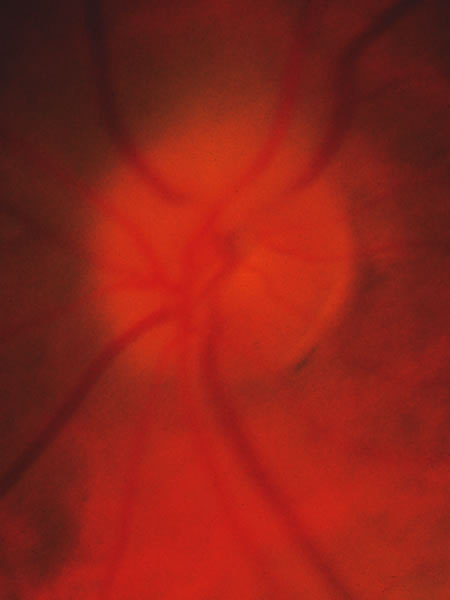

Fig. 33. Swollen disc tissue during an acute attack of angle closure glaucoma.

In acute angle-closure glaucoma (Fig. 33), the optic disc may swell,147–149 perhaps as a result of ischemia, but because of corneal edema and preoccupation with the angle status, it is not often seen. Even after an attack lasting several days, there is often no visual loss; the disc may remain normal appearing or may develop some degree of pallor resembling that of nonglaucomatous optic atrophy.150–152 Excavation of the disc does not seem to result from an acute attack but may result from persistent residual pressure elevation after the attack. If excavation is already present at the time that a patient presents with symptomatic angle closure, the cupping is evidence that for some time an asymptomatic, perhaps gradual, rise of intraocular pressure elevation preceded the abrupt onset of symptoms.